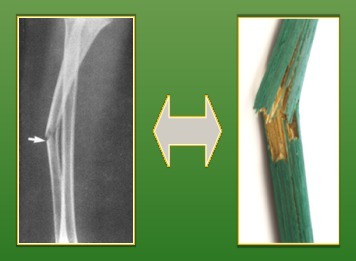

Greenstick fracture: incomplete fracture of long bones usually seen in young children < 10 years age